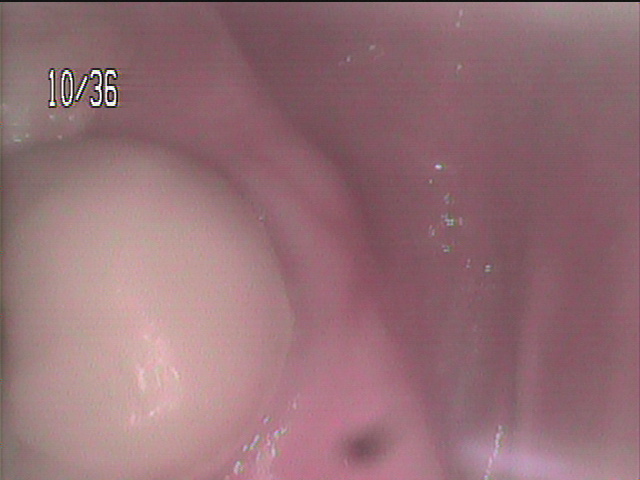

かなり下に、炎症が起こり腫脹しています。

かなり激しい炎症があるため

痛みがあります。この後症状が重くなることが

想定できるので、なるべく早く根管治療と

抗生物質 消炎鎮痛剤が必要です。